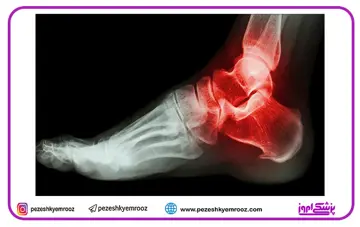

علت خار پاشنه ، نشانه‌ها ، علائم و درمان

خار پاشنه که طی مدت طولانی ایجاد می‌شود، اغلب به دنبال اعمال نیروی کششی (Strain) مستمر روی عضلات و لیگامان‌های پا (Foot) ، کشش نیام کف پایی و پارگی مکرر غشای پوشاننده استخوان پاشنه به وجود می آید.به همین دلیل این عارضه به ویژه در ورزشکارانی که سطوح بالایی از دویدن و پرش را حین ورزش کردن تجربه می‌کنند، رایج است.